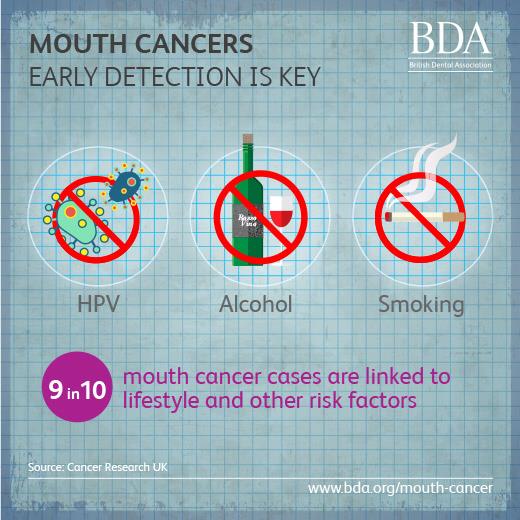

Tobacco is the leading cause of mouth cancer – which has seen a 135% increase in cases over the last 20 years in the UK. #ActOnTobacco Matt Hancock Steve Brine MP and support calls for a rise in the minimum purchasing age & a levy on the tobacco industry. bit.ly/2H9vS2t

Mouth cancer has increased by 135% and many of us do not know the early warning signs and symptoms. Oral Health Foundation #OralHealth #MouthCancer #DentalHealth dentalhealth.org/news/mouth-can…